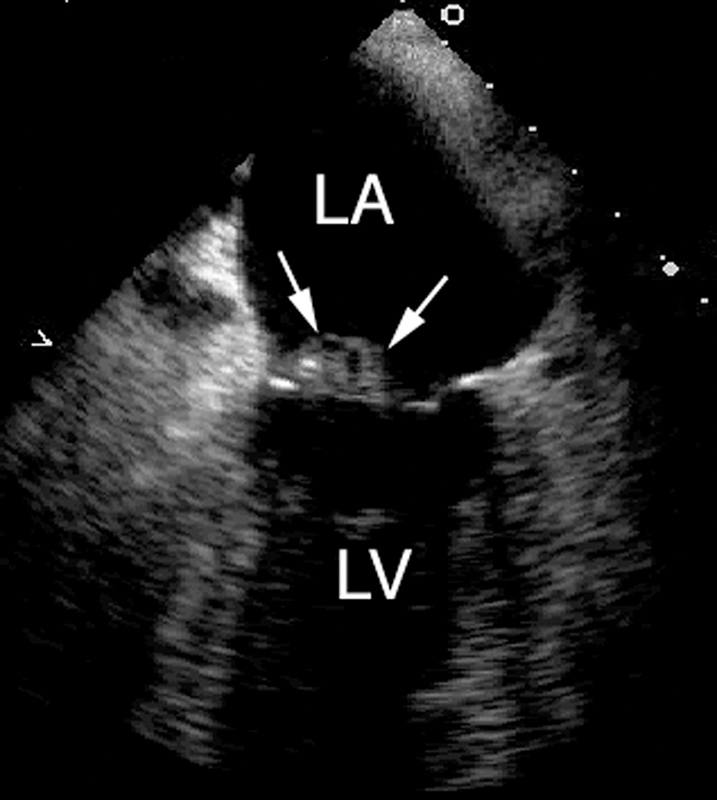

فحوصات تشخيصية لبعض امراض القلب والشرايين التاجية